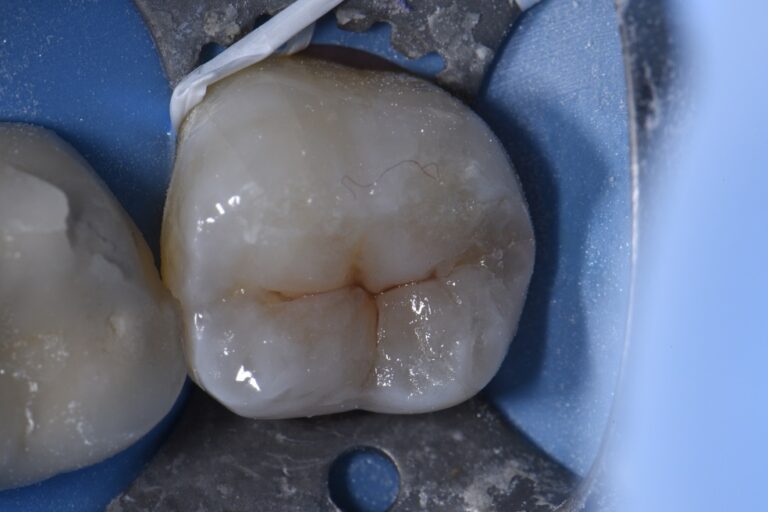

From www.clarencetam.co.nz

Chasing vertical hairline fractures Hairline Fracture Tooth Symptoms Symptoms of a hairline tooth fracture. The symptoms of a hairline fracture in a tooth can vary depending on the severity of the crack and its location. Sensitivity to hot and cold temperatures: If these cracks don’t affect appearance and don’t produce pain, your doctor may advise leaving them alone. A hairline crack in a tooth, also called a craze. Hairline Fracture Tooth Symptoms.

Chasing Hairline Fractures in Molars Hairline Fracture Tooth Symptoms The symptoms of a hairline cracked tooth can be subtle, but there are signs you can watch for, including: If you experience pain or discomfort when consuming hot or cold foods or drinks, this could be a sign of a hairline fracture. If these cracks don’t affect appearance and don’t produce pain, your doctor may advise leaving them alone. Not. Hairline Fracture Tooth Symptoms.